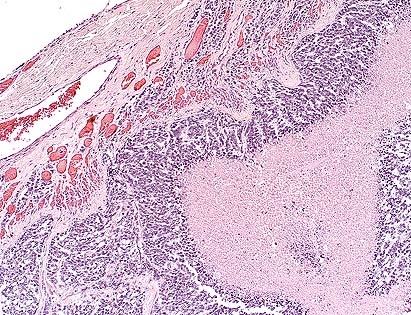

High-grade astrocytoma in the cerebrum of a rhesus monkey showing characteristic palisading of neoplastic cells along areas of necrosis. (HE, 40X, 54K)

Astrocytomas generally occur as soft tissue masses in the substance of the cerebral hemispheres, and produce a spectrum of clinical signs based on their exact location. The majority of astrocytomas are well-differentiated with a relatively uniform population of transformed astrocytes having oval nuclei, little heterochromatin and poorly defined cell borders. The tumors can be graded, but regardless of grade there is a background of astrocytic processes between neoplastic nuclei. Higher grade astrocytomas are characterized by increasing nuclear anaplasia, mitotic activity and vascular proliferation. In the adjacent parenchyma, endothelial cells may form glomeruloid proliferations within vascular lumina. These are prominent in high grade astrocytomas, and were present in this case. The highest grade astrocytomas are usually very cellular, and have a mixture of firm white areas, and softer yellow foci of necrosis. These latter features, especially the presence of necrosis, have given rise to the term glioblastoma multiforme. Immunohistochemistry performed by AFIP was positive for glial fibrillary acidic protein (GFAP) and negative for S100, synaptophysin, cytokeratin, and vimentin.

Conference Note: This case has classic features of glioblastoma multiforme, which is often simply called high grade astrocytoma. These features include high cellularity, pleomorphism, necrosis, subpial spread, cortical infiltration, necrosis surrounded by "pseudopalisades" and areas of glomerulus-like endothelial proliferation. Recent evidence suggests that vascular endothelial cell growth factor (VEGF) is secreted by malignant astrocytes perhaps in response to hypoxia.